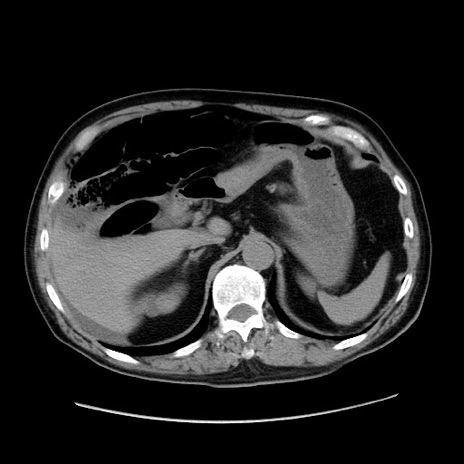

冠状断像